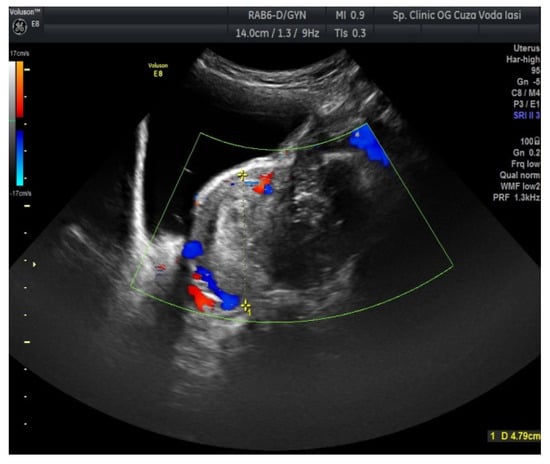

2. Case Presentation